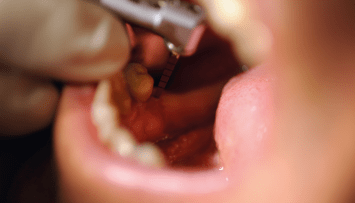

Die Endodontie hat in den vergangenen Jahren einen immensen Fortschritt erlebt. So können heute mit Zuhilfenahme moderner Geräte und Techniken auch Zähne erfolgreich erhalten werden, die noch vor geraumer Zeit als nicht erhaltungsfähig galten.